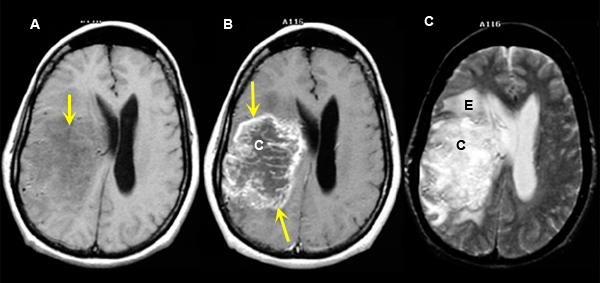

Figure 2

A:

Pre-contrast axial T1 wtd. MRI

B.

Post-contrast axial T1 wtd. MRI

C.

Axial T2 wtd. MRI |

Imaging findings: Figure 2

- Non-specific abnormality within the right deep frontal lobe (arrow) with mass effect upon the right lateral ventricle is noted on pre contrast T1 wtd. image (fig. A.)

- Tumor demonstrates irregular peripheral enhancement (yellow arrows) with central area of cystic necrosis (C in fig. B).

- Edema (E) / cystic necrosis is visible as an area of bright signal intensity on T2 wtd. image.

Final impression:

Classic right deep frontal lobe glioblastoma demonstrating irregular peripheral ring enhancement with central area of cystic necrosis and surrounding edema. |